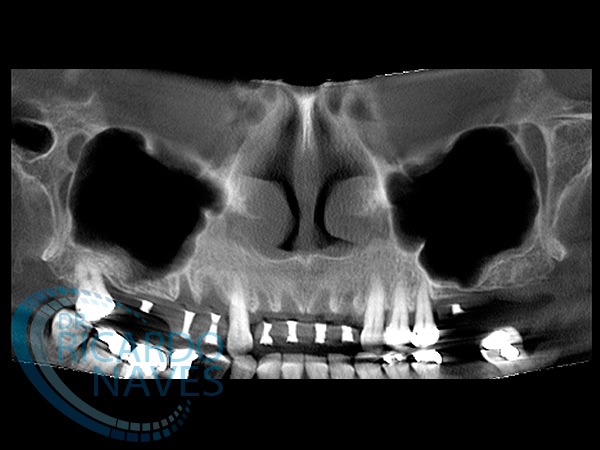

Obsérvese la gran atrofia a nivel de senos maxilares en donde seria imposible instalar implantes sin instalar injertos.

Tomografía post exodoncias con marcadores radio opacos en prótesis de trabajo.